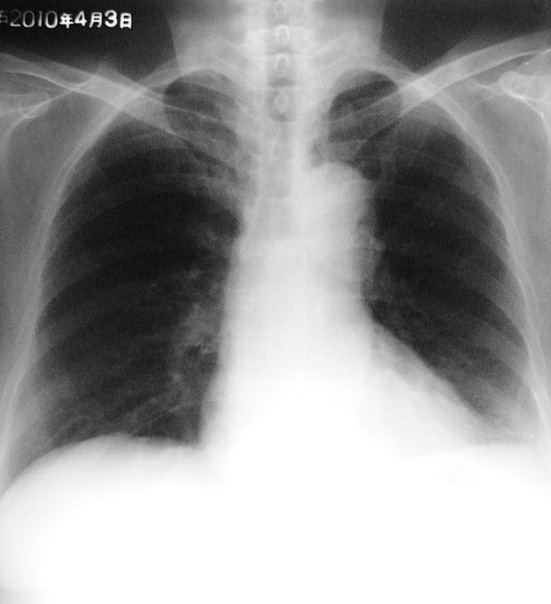

标题: X7067:胸部平片

女,68岁,咳嗽、咯血(血丝)一周。余其它状况良好~~

左侧肋膈角变钝

未见明显异常,做个ct看有没有局灶性支扩。

胸部平片未见异常。

平片阴性,ct可能阳性.

平片未见明显异常,建议hrct看有否支扩表现。

左侧少量胸腔积液;左侧膈肌略抬高,建议ct检查。

体胖老年妇女,肋膈角处可能是乳房影,胸部未见明显异常改变,有症状,建议ct进一步检查,以免误诊